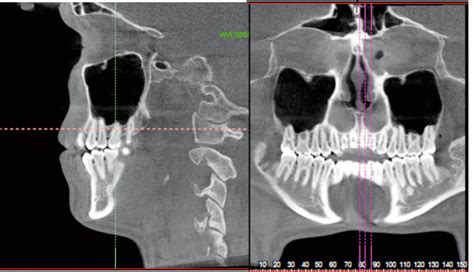

Además, la sinusitis maxilar, una inflamación de los senos paranasales ubicados en las mejillas, puede causar dolor en la encía cerca de la nariz. Esta condición puede ser causada por infecciones bacterianas, virales o fúngicas, así como por alergias o problemas estructurales en la cavidad nasal.

Sinusitis Maxilar y su Relación con el Dolor de Encías

La sinusitis maxilar puede tener un impacto en la salud bucal. Los senos maxilares están cerca de los dientes superiores, y la inflamación o infección en estos senos puede causar dolor en la zona de los molares superiores o en las encías.

La sinusitis de los senos maxilares por infección dental ocurre cuando una infección dental se propaga a través de los tejidos circundantes y alcanza los senos maxilares. Los síntomas incluyen:

Estos síntomas pueden confundirse con problemas dentales, lo que subraya la importancia de un diagnóstico preciso por parte de los profesionales dentales.